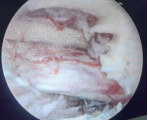

4.微创脊柱内镜技术:PELD+UBE+OSE

脊柱内镜技术是一项开展较早的脊柱外科微创技术,与传统开放手术相比,它是借助天然解剖间隙建立微创工作通道,解除神经压迫;对椎旁肌肉损伤较小,且能够最大程度地保留完整的脊柱结构,维持了术后脊柱的稳定,具有创伤小、出血少、恢复快、并发症少、疗效确切等优点。目前已开展椎间孔镜下髓核摘除术,单侧双通道脊柱内镜(UBE)下椎管减压术并处于区域内领先水平。好看视频下载

在江苏省内率先开展了单孔分体式脊柱内镜技术(OSE),处国内领先水平。

单孔孔镜

单侧双通道技术

单孔分体式内镜下腰椎固定融合技术